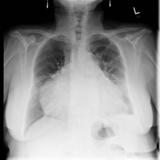

Cong Abscence of Peric

Date: 03/17/2004

Views: 3051